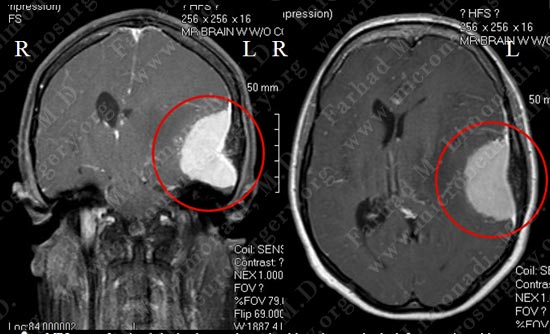

MRI scan of patient's brain shows a large dural based tumor in the left convexity with significant vasogenic edema and midline shift.